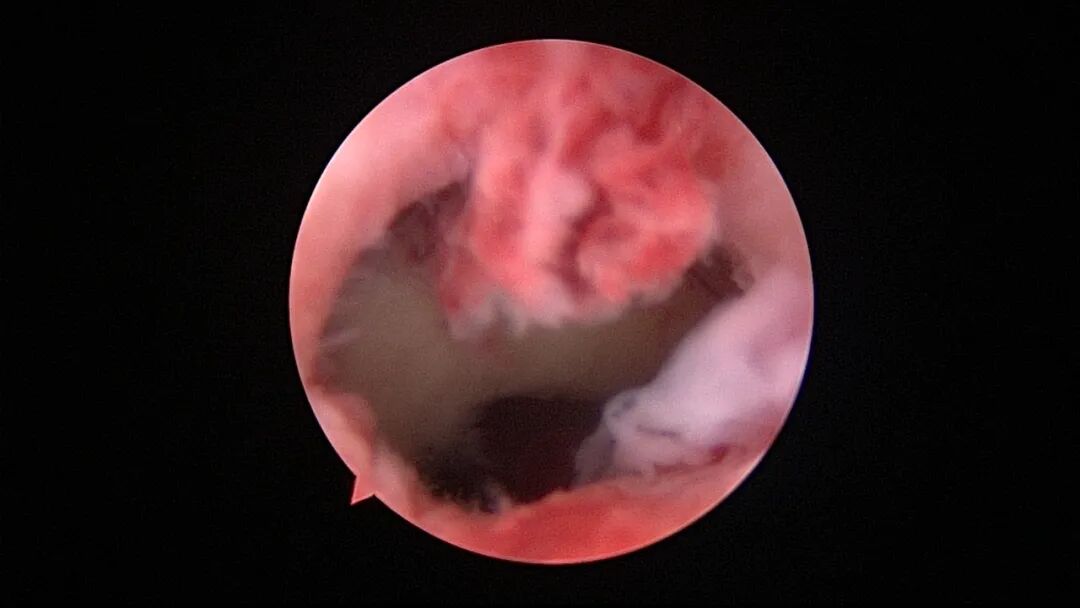

外院取环失败,子宫从切口憩室处穿孔